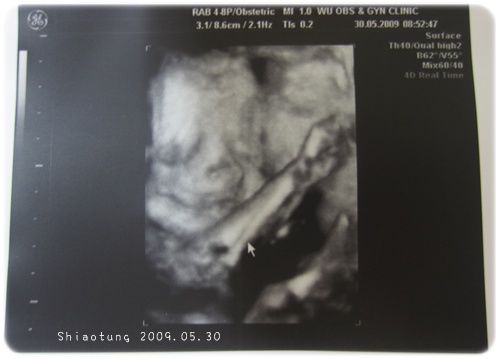

醫生一看到這張就說很像靚靚,

哈哈哈哈...哪裡像?

這明明就是扮鬼臉,

眼皮還往下...

這是當初靚靚25+時候。

兩人像我看都是手很愛遮臉吧!